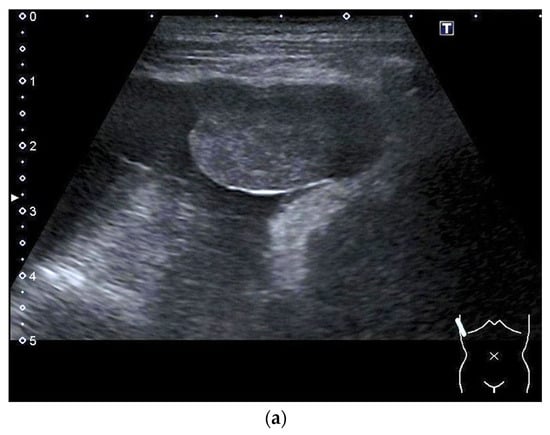

Contrast-Enhanced Ultrasound (CEUS) of the Lung and Pleura